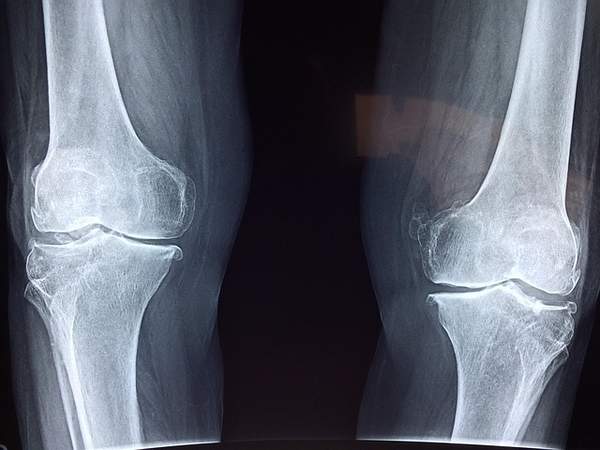

올바른서울병원 정형외과는 다양한 정형외과 질환을 진료합니다. 관절염, 퇴행성 관절 질환, 골절, 인대 손상, 척추 질환 등 다양한 분야에서 전문적인 치료를 제공합니다.

특히, 무릎 관절염, 허리 디스크, 목 디스크와 같은 흔한 질환부터, 골다공증, 류마티스 관절염과 같은 좀 더 전문적인 치료가 필요한 질환까지, 숙련된 의료진이 정확한 진단과 함께 환자 개인의 상태에 맞는 최적의 치료법을 제시합니다.

올바른서울병원 정형외과는 최첨단 의료 장비를 통해 정확한 진단과 효과적인 치료를 제공합니다. MRI, CT, X-ray 등 최신 영상 장비를 통해 환자의 상태를 정확하게 파악하고, 개인별 맞춤 치료 계획을 세웁니다.